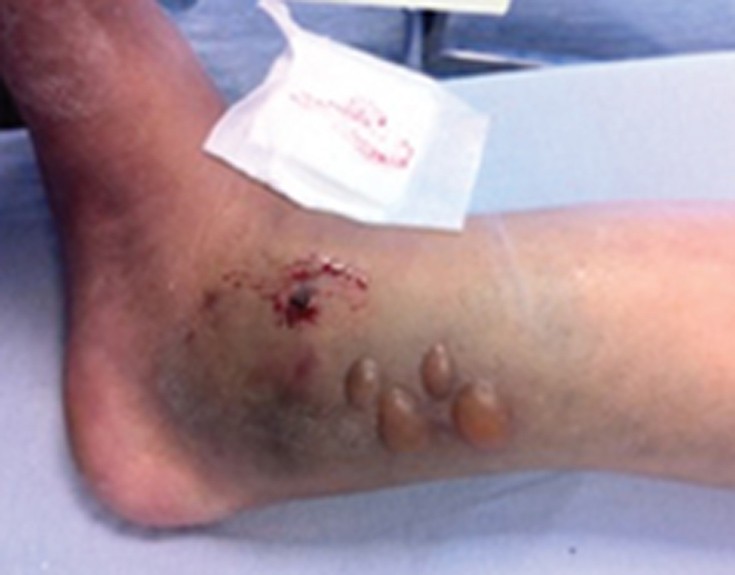

Μέχρι να φτάσουμε σε νοσοκομείο πρέπει το πόδι να τοποθετηθεί πολύ ψηλά! Γιατί τα κατάγματα των σφυρών προκαλούν λόγω μεγάλου οιδήματος, μεγάλες φυσαλίδες στο δέρμα με υγρό, και δεν επιτρέπουν την εγχείρηση. Σπανίως μπορεί να προκαλέσουν και νέκρωση στο δέρμα.